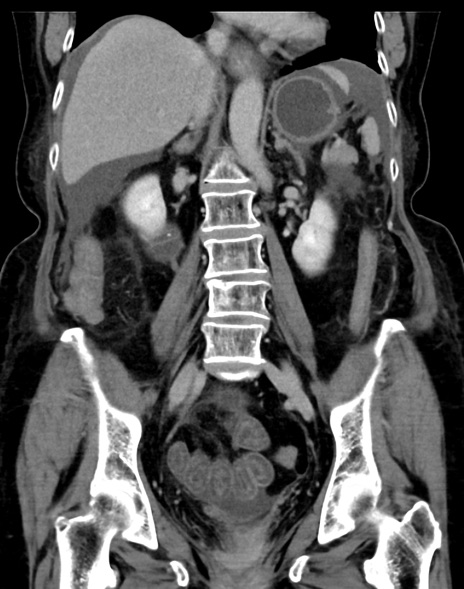

症例13 CT(冠状断像)1日半後